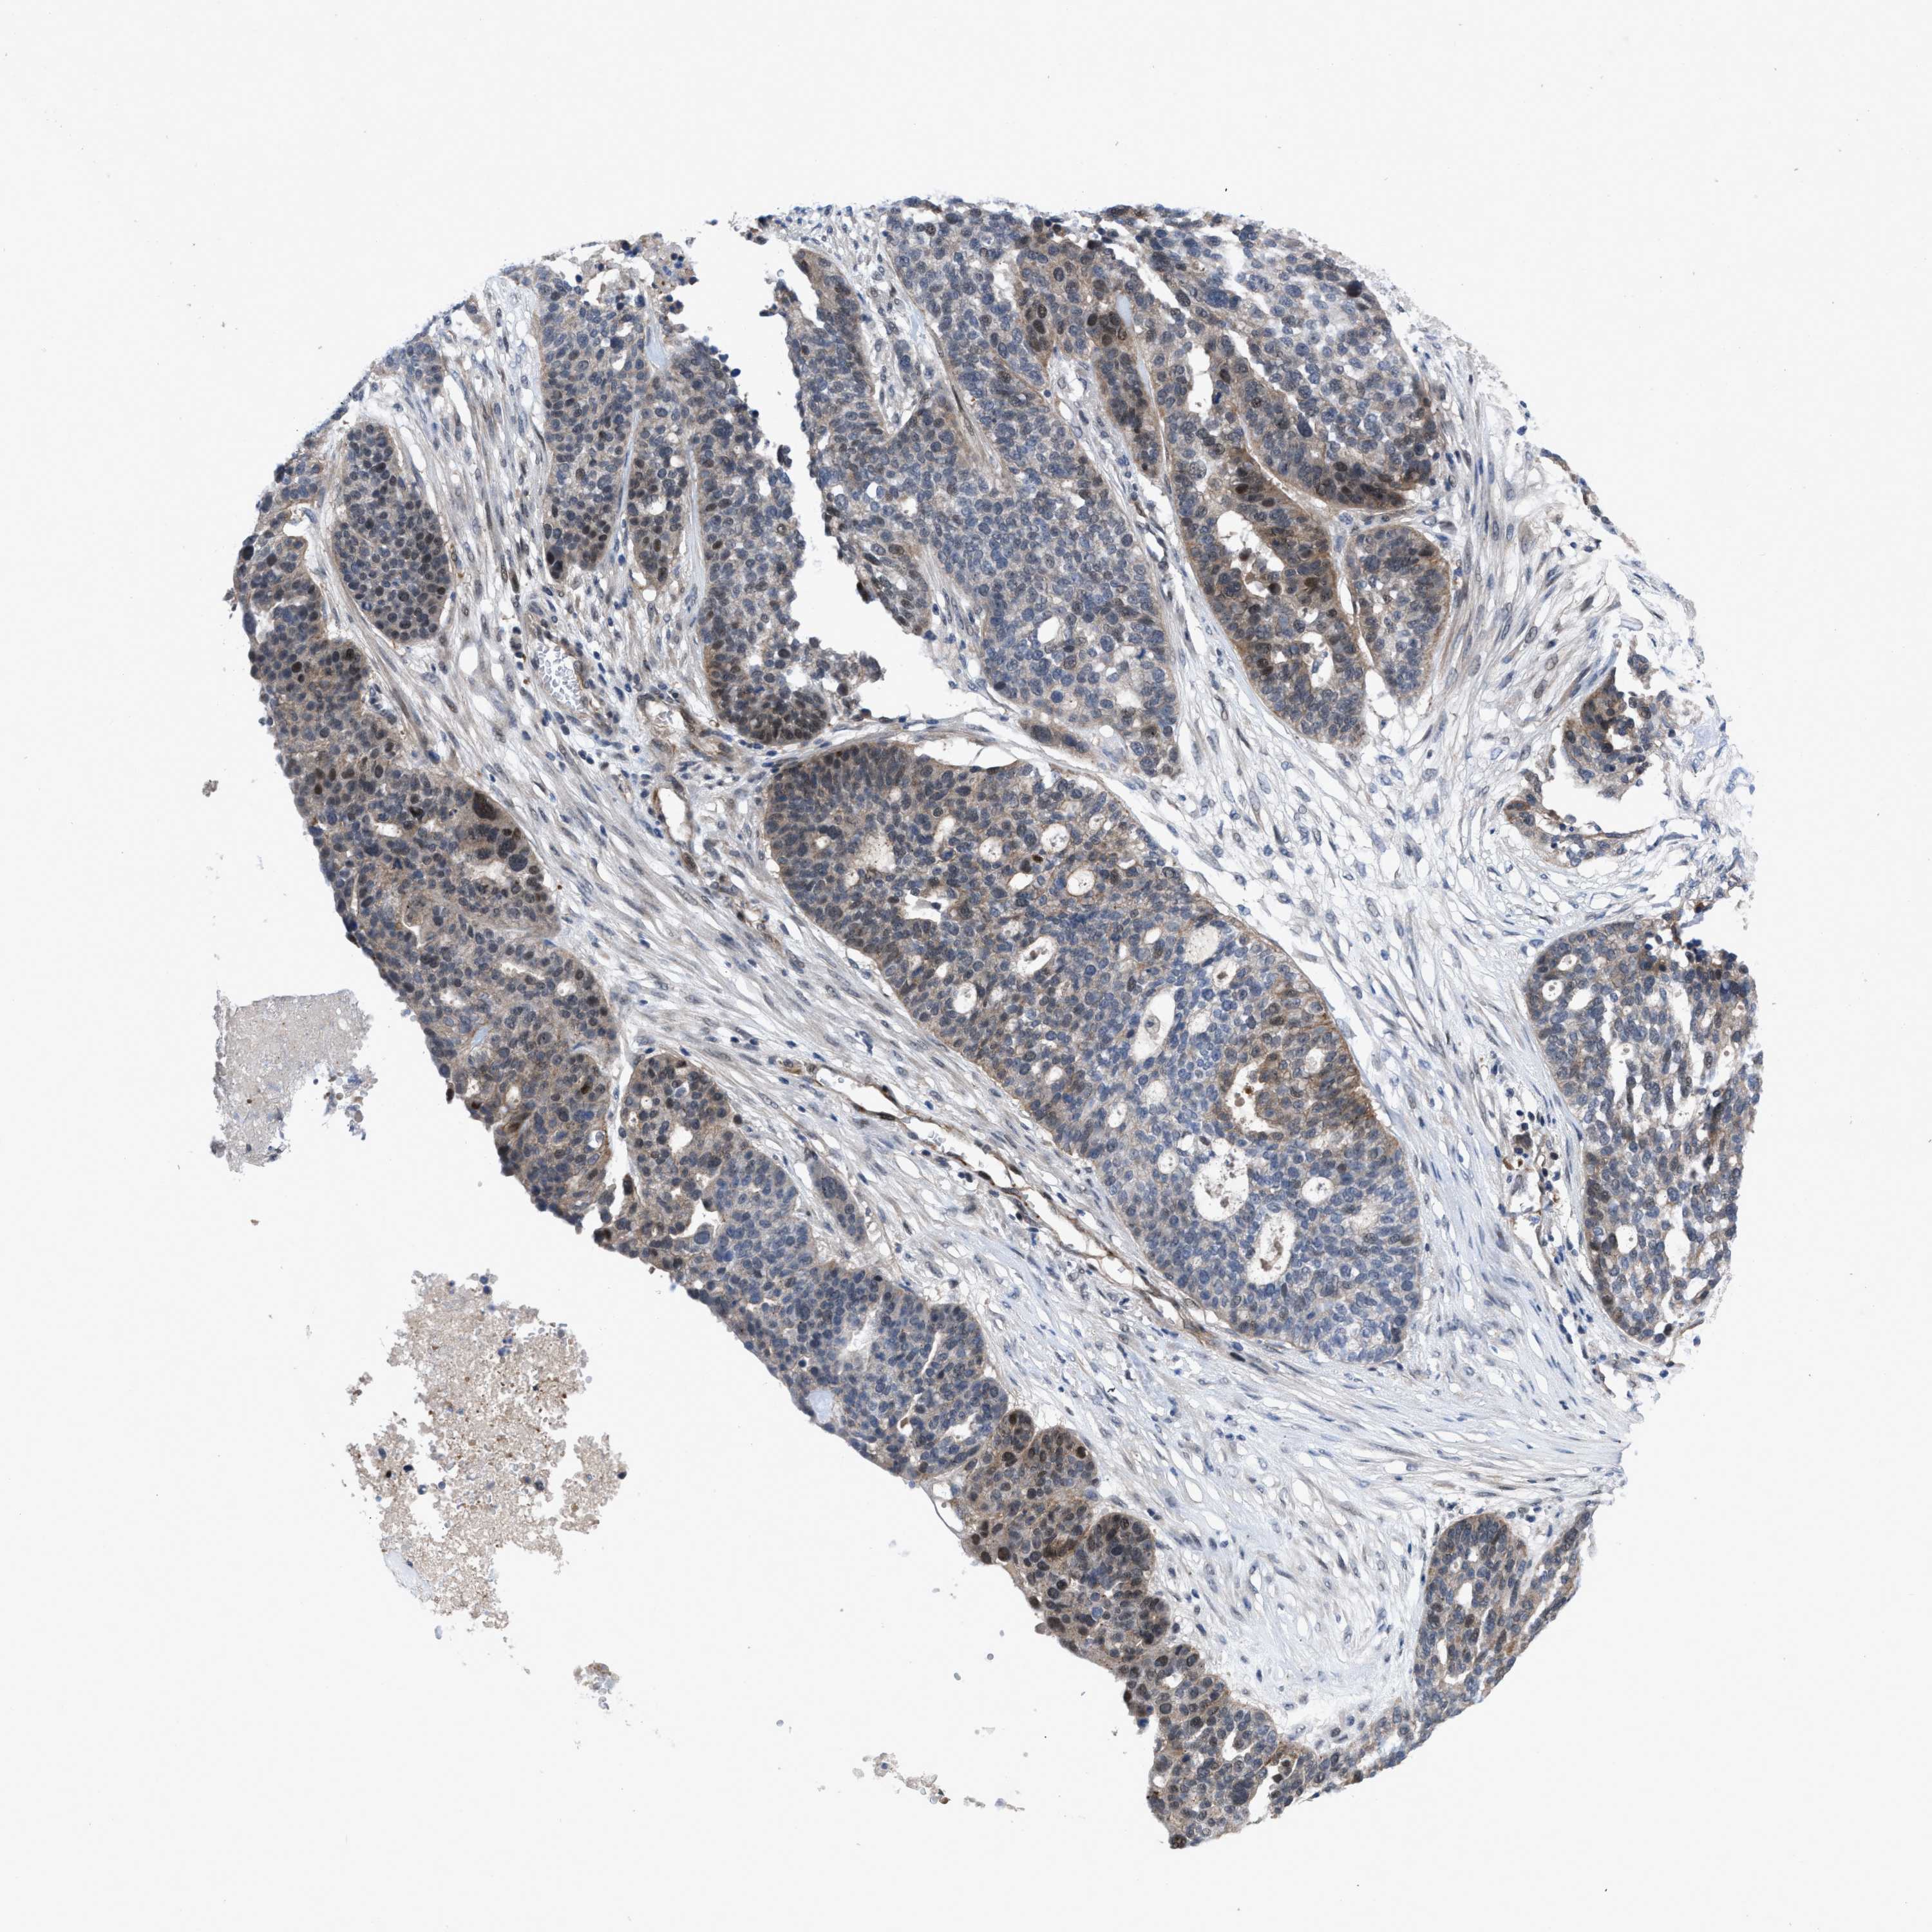

OVARIAN CANCER - Protein expressioni

A mouse-over function shows sample information and annotation data. Click on an image to view it in a full screen mode. Samples can be filtered based on level of antibody staining by selecting one or several of the following categories: high, medium, low and not detected. The assay and annotation is described here.

Note that samples used for immunohistochemistry by the Human Protein Atlas do not correspond to samples in the TCGA dataset.

Antibody stainingi

Antibody staining in the annotated cell types in the current human tissue is reported as not detected, low, medium, or high, based on conventional immunohistochemistry profiling in selected tissues. This score is based on the combination of the staining intensity and fraction of stained cells.

Each image is clickable and will lead to virtual microscopy that enables deeper exploration of all samples and also displays staining intensity scores, fraction scores and subcellular localization as well as patient and tissue information for each sample.

Antibody HPA019011

Staining

High

Medium

Low

Not detected

Intensity

Strong

Moderate

Weak

Negative

Quantity

>75%

75%-25%

<25%

None

Location

Nuclear

Cytoplasmic/membranous

Cytoplasmic/membranous,nuclear

Cystadenocarcinoma, serous, NOS

Carcinoma, endometroid

Cystadenocarcinoma, mucinous, NOS

Carcinoma, NOS